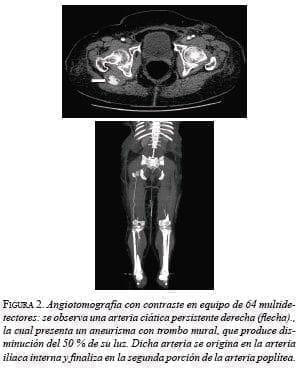

Se consideró que la causa de la isquemia aguda fue la embolia desde el aneurisma de la arteria ciática persistente y que la mayoría del flujo de la extremidad estaba dado por dicha arteria anómala. Con el fin de planear la corrección del aneurisma de la arteria ciática persistente, para evitar eventos isquémicos posteriores, se practicó una angiotomografía de los miembros inferiores (figura 2).